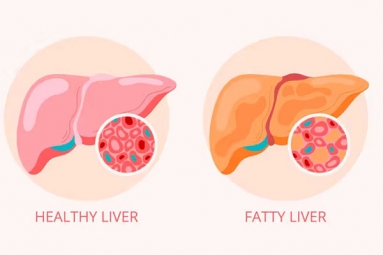

Liver issues, previously associated with older ages, are now becoming common in younger people too. A frequently encountered problem among today’s youth is non-alcoholic fatty liver disease (NAFLD). This condition is on the rise in young adults, largely due to unhealthy lifestyles, bad eating habits, overweight, and obesity. If not addressed promptly, a fatty liver can lead to serious health issues like non-alcoholic steatohepatitis (NASH), liver fibrosis, cirrhosis, or even liver cancer. There’s no need to panic just yet.

Losing Weight: By enhancing your physical activity or adding a fitness routine to your life and maintaining a balanced diet, you'll begin to shed fat and lose extra weight.Slowly and consistently losing weight can be life-changing and is known to be one of the best methods to reverse fatty liver.